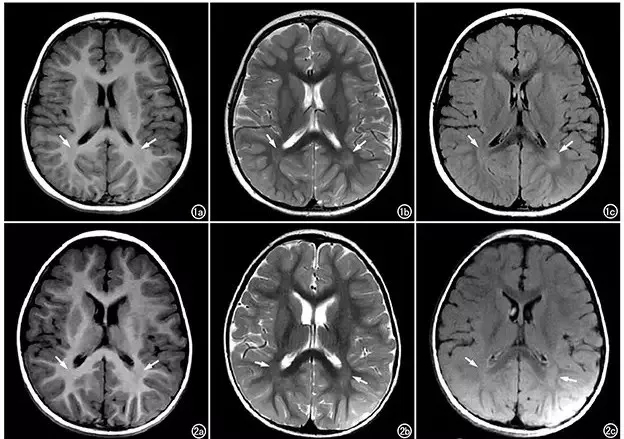

比如:脑部核磁,了解脑发育情况

判断神经系统有无损害及损害的部位和程度,即解决病变的“定位”诊断。

△下图为一个3岁男孩语言发育迟缓,CT图